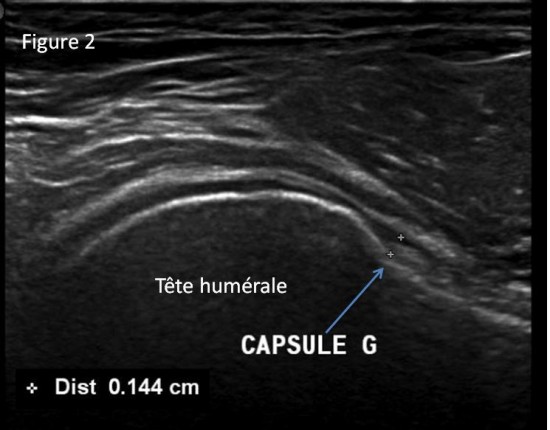

Patient de 44 ans presentant une masse peu sensible de la face palmaire du poignet avec des.

Une anomalie des membres caracterisee par labsence congenitale dun membre a partir du coude. Tumeurs pseudo tumeurs thrombose veineuse ulnaire du poignet irm.